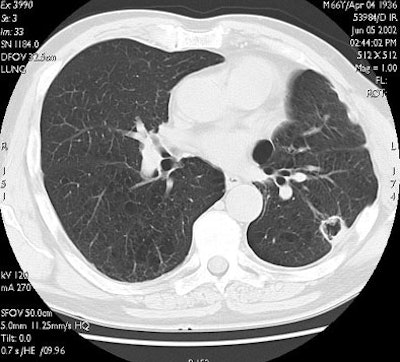

CT follow-up occurred one and three months after the procedure and at three-month intervals thereafter. Eleven of 13 lesions followed up for at least six months continued to shrink and had no CT-detectable viable tumor, and complete ablation was confirmed for all eight lesions that were followed for a year or more, he said.

"Here you can see one of the cases with a one-year follow-up. The tumor is replaced by a volume of coagulation, which is in excess with respect to the size of the native lesion, and then at three months, six months, and one year there is progressive shrinkage of the coagulation, with some cavitation detectable on CT," he said.